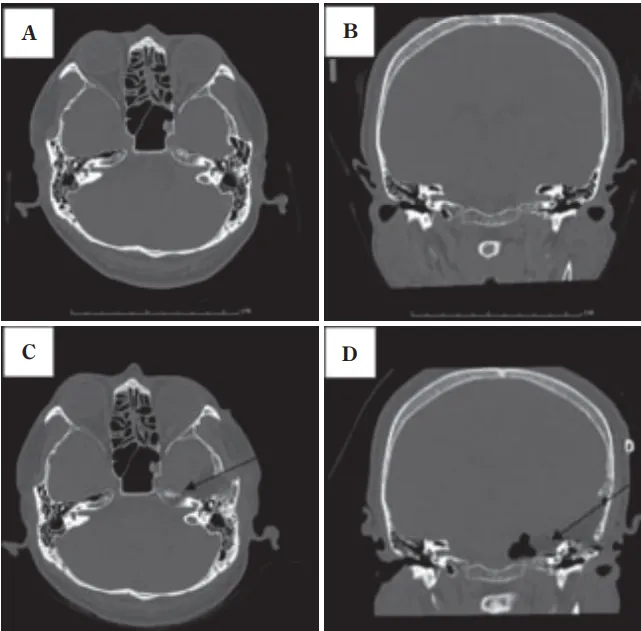

术后患者出现面神经麻痹症状,经一年恢复期后明显改善。复查影像显示内耳道前壁与上壁切除范围精确,颈静脉球保护完整,肿瘤全切无复发迹象。

A&B:术前轴位与冠位CT图像,显示岩骨水平内耳道。巨大高位颈静脉球突入后颅窝

C&D:术后图像显示内耳道前壁与上壁切除范围